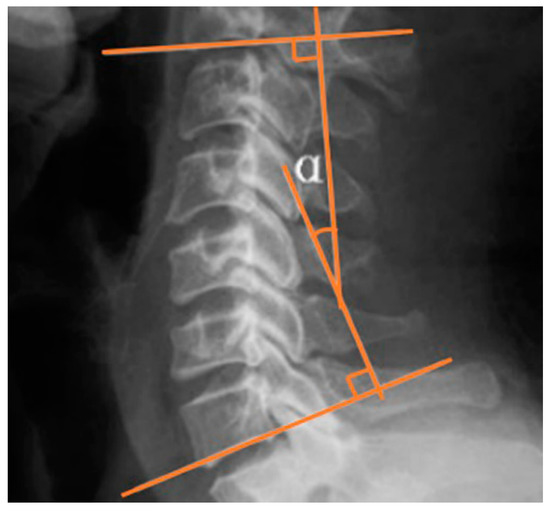

2.4.1. Cervical Lordotic Curve

| Cobb angle at C2–7 (°) | 4.8 ± 10.9 | 16.9 ± 12.7 | <0.001 * |

| Cobb angle at C2–7 (°) | 5.2 ± 8.6 | 4.9 ± 9.8 | 0.781 |

| Cobb angle | 10.1 ± 4.5 | −0.3 ± 5.3 | 7.6 | <0.001 * |